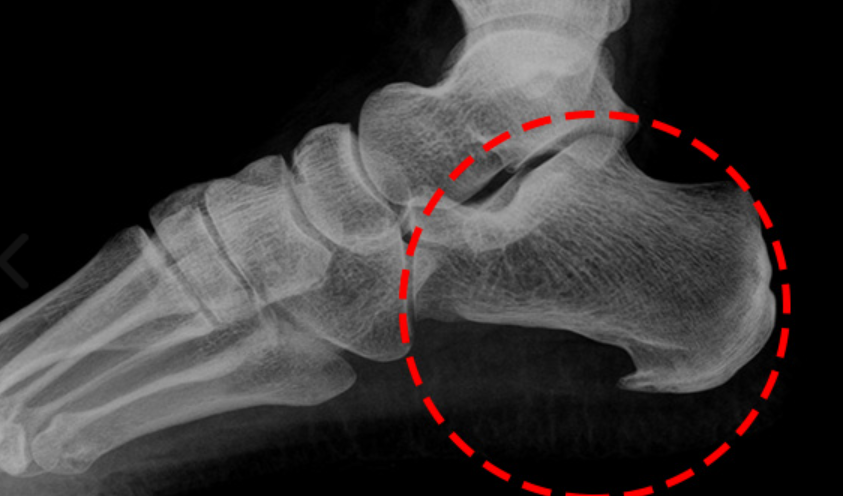

족저 근막은 종골에서 시작하여 발바닥 앞쪽으로 5개의 분지를 내어 발가락 기저부에 부착되는 강인하고 두꺼운 섬유띠입니다.

이는 발의 아치(arch)를 유지하고 체중 부하 상태에서 발을 올리는 데 도움을 줍니다. 발의 역학에 중요한 역할을 하는 부위입니다.

족저 근막염은 임상에서 가장 흔하게 접하게 되는 족부 병변 중 하나로, 뒤꿈치의 통증을 일으키는 질환입니다. 이 질환의 평균 발병 연령은 45세 정도입니다.